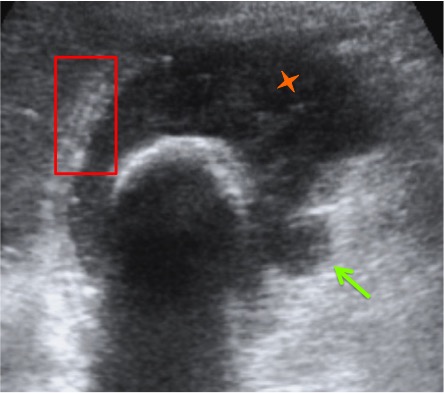

Se realiza ecografía abdominal:

En sucesivos cortes observamos lo siguiente:

Se observa una mala evolución radiológica. Dada la clínica del paciente y los hallazgos ecográficos podemos concluir que estos hallazgos son compatibles una colecistitis xantunogranulomatosa litiásica sobreinfectada (que se confirmó posteriormente con anatomía patológica).

- Colecistitis xantunogranulomatosa: nódulos o bandas intramurales. Se producen por la oclusión de los senos de Rokitansky Aschoff de la pared, los cuales se rompen, luego la bilis coloniza la pared y finalmente produce una reacción inflamatoria a la que puede sobreañadirse una infección. Es un factor de riesgo para el carcinoma.

- Eco y TC: Litiasis + engrosamiento mural focal o difuso. Puede haber cambios inflamatorios pericolecísiticos. Los nódulos hipocogénicos o bandas pueden sugerir el diagnóstico específico de c. xantunogranulomatosa.